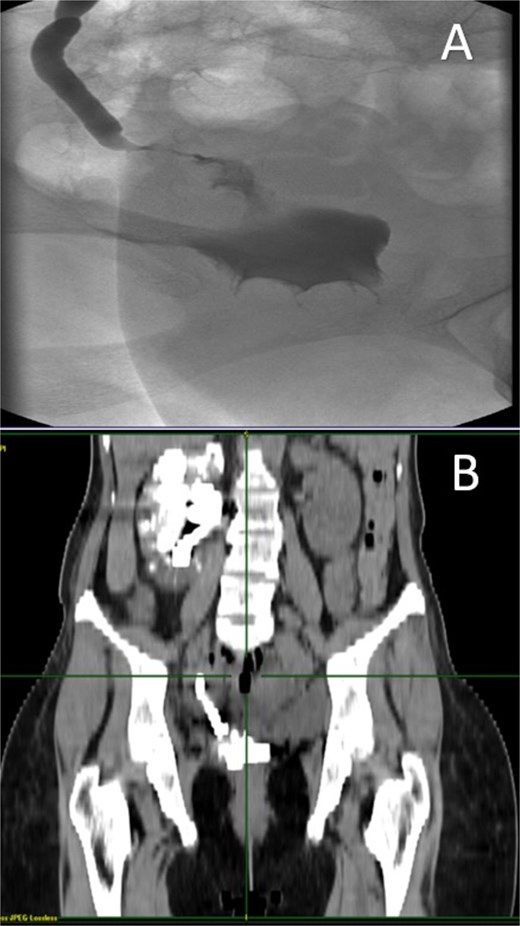

Two months later, the symptoms gradually reoccurred and a retrograde cystography and CT cystography were performed demonstrating the known UVF and as a new finding the formation of a VVF (Fig. 2). Based on these findings, a surgical repair with an open abdominal exploration was decided.

A: Retrograde cystography with contrast enhancement showing the existence of a VVF. B and C: CT cystography showing passage of contrast enhancement from the bladder to vagina, demonstrating the formation of a VVF.